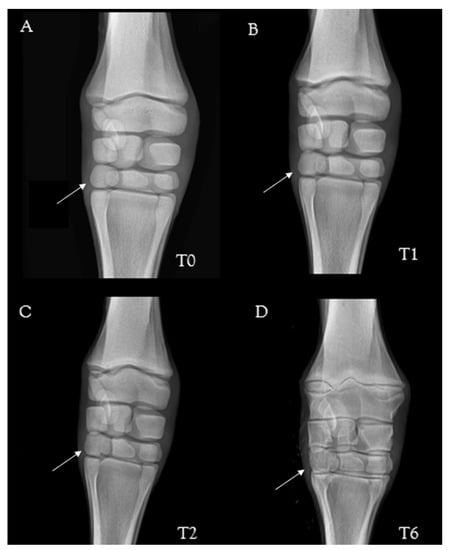

2.3. Radiological Parameters